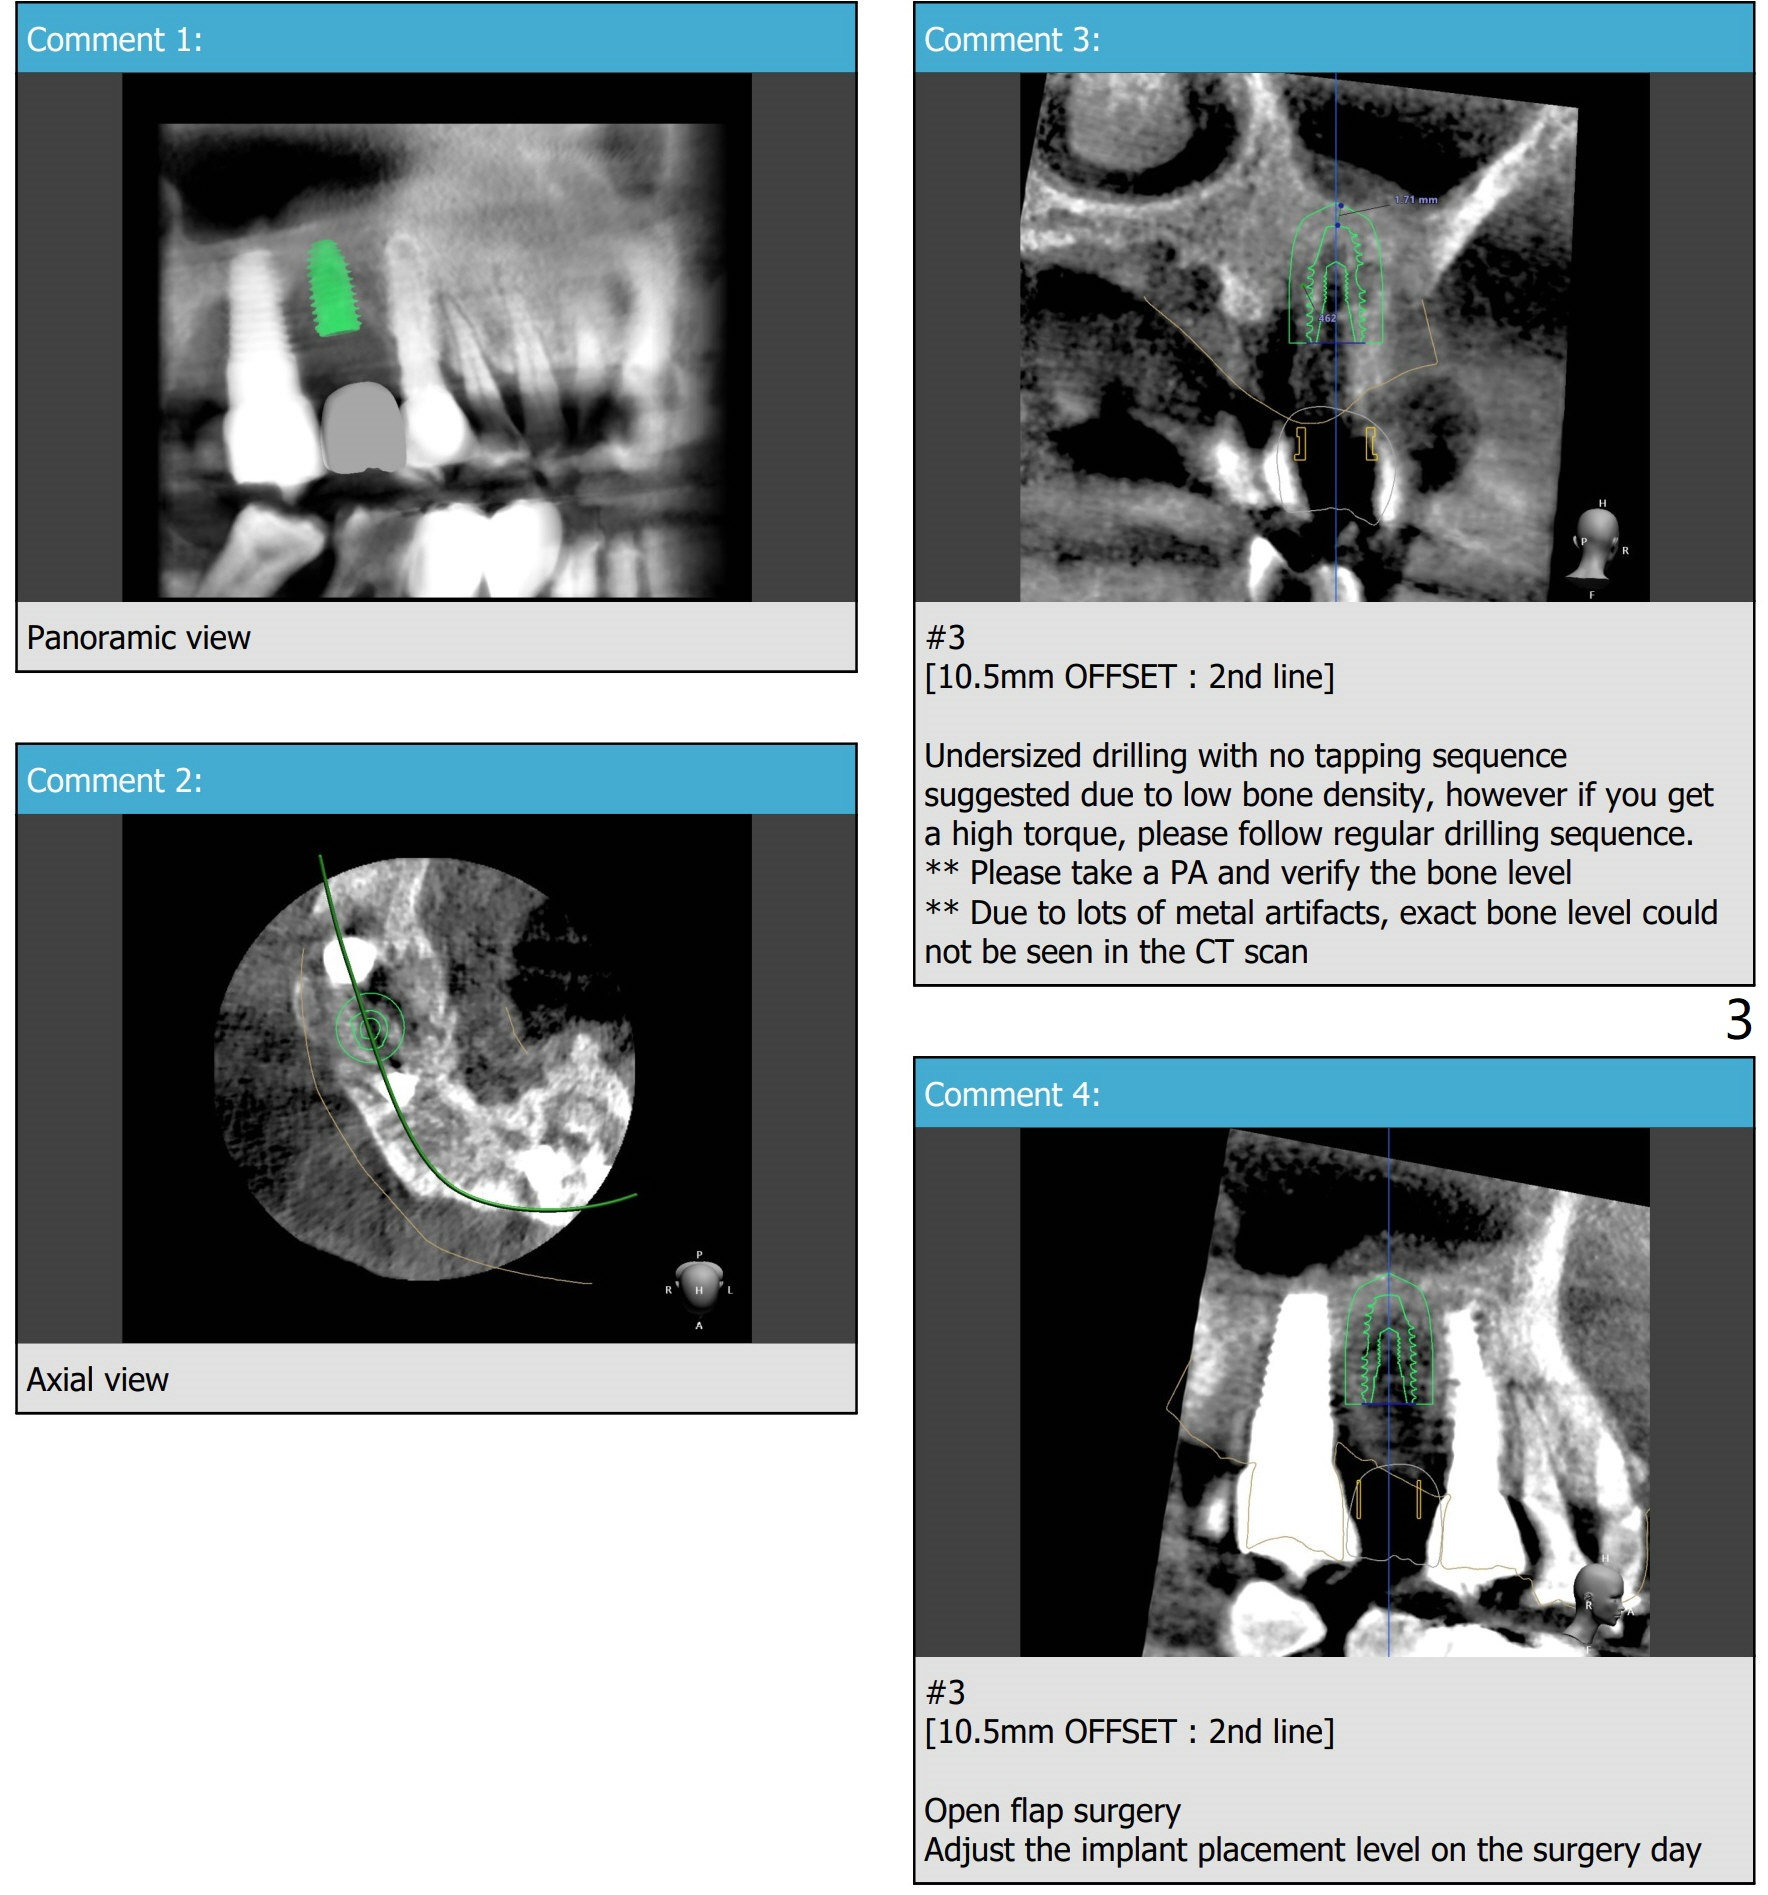

Low Density, Murky Bone Boundary

A -year-old man.  PRFx2